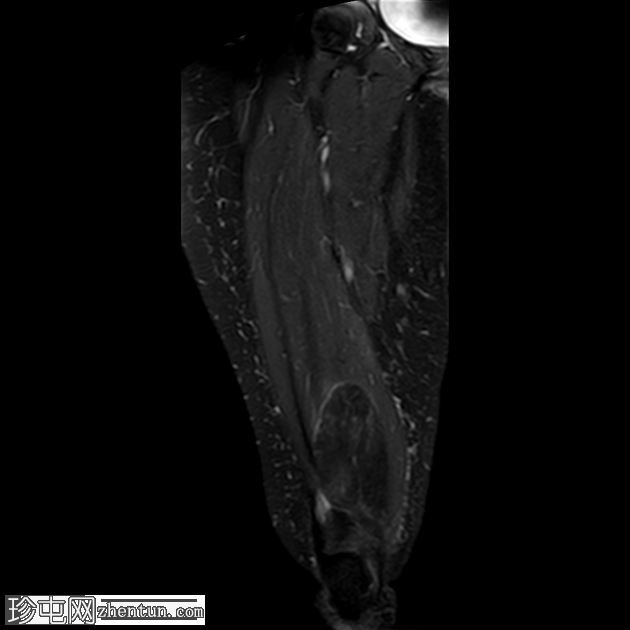

冠状位

T2加权像

3.png

STIR序列

可见一较大的、边界清晰的肌内肿块,主要累及股内侧肌及部分股中间肌。

病灶大小:4.3 x 5.2 x 12.6 cm(前后径 x 横径 x 头尾径)

信号特征:

T1加权像:均匀高信号,与皮下脂肪信号相同

T2加权像:均匀高信号,与皮下脂肪信号相同

PD脂肪抑制/STIR序列:信号均匀抑制,呈低信号,与皮下脂肪信号相同

未见内部增厚或结节状非脂肪性间隔,也未见强化实性成分。

边缘:光滑,呈分叶状,有一层薄的纤维包膜。

邻近结构:未见皮质凹陷、骨髓水肿或侵犯。

未见筋膜破裂、肌肉浸润或周围水肿。

以上特征符合良性肌内脂肪瘤的诊断。